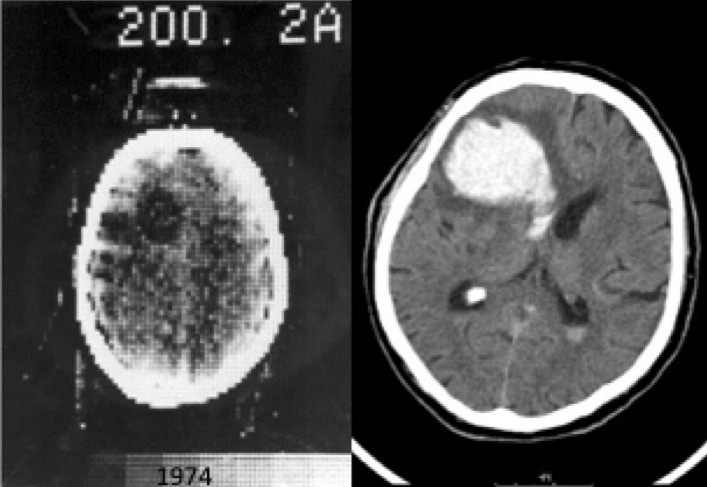

Der EMI Mark I, der 1972 in Betrieb genommen wurde, erzeugte erstmals Querschnittsbilder des menschlichen Kopfes. Der Tomograf arbeitete auf Basis von Röntgenstrahlen, die den Körper aus verschiedenen Richtungen durchstrahlten und von Detektoren auf der gegenüberliegenden Seite aufgezeichnet wurden. Der Computer berechnete aus diesen multiplen Projektionsdaten detaillierte Schnittbilder. Die Erfindung war eine Sensation: Bereits 1979, also sieben Jahre nach dem ersten klinischen CT-Scan, erhielten Cormark und Hounsfield den Nobelpreis für Medizin.

Entwicklung der Bildqualität in der CT: Links eine Kopfaufnahme von 1974, rechts ein 50 Jahre später erzeugtes Bild.